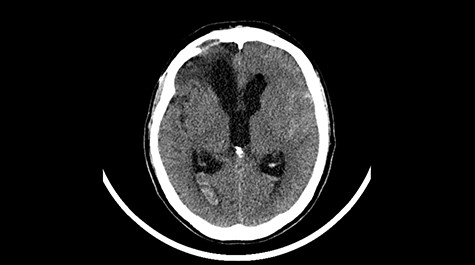

A 49-year-old patient presented after surgical treatment of nasal polyps, with headache and consciousness disorders (behavioral changes, drowsiness and allophenic orientation disorders). Computed tomography (CT) scan showed (Fig. 1) a presence of blood in fluid spaces, widening of the ventricular system (without active hydrocephalus features) and presence of air in the frontal horns of the lateral ventricles and features of cerebral edema. Due to the subarachnoid hemorrhage, an angio-CT and CT scan was performed, showing no vascular malformation. The patient's condition deteriorated with a drop in Glasgow Coma Scale (GCS) to 9, strongly expressed meningeal syndrome and a fever of > 38°C. In the performed cerebrospinal fluid examination a typical picture for bacterial infection, cultures negative. Treatment was implemented in accordance with the neuro-infections algorithm. Clinical and laboratory features of neuroinfections have withdrawn. The neurological condition of the patient improved to GCS 11. Control head CT (Fig. 2) showed enlargement of the ventricular system with cerebrospinal fluid transudation.

Head CT after polypectomy—presence of blood in fluid spaces, widening of the ventricular system, presence of air in the frontal horns of the lateral ventricles, features of cerebral edema. (Department of Neurosurgery Neurotraumatology and Pediatric Surgery own material).

In described case, a head CT scan after polypectomy confirmed the subarachnoid hemorrhage (Fig. 1). In addition, the presence of air in the ventricular system was visible, and presence of defects of the upper left orbital wall and ethmoid on both sides (Fig. 3). In the CT scan sphenoid sinus, frontal and ethmoidal sinuses on both sides and right maxillary sinus airless, filled with blood and soft tissue. The changes also concerned the lateral part of the left maxillary sinus (Fig. 4).